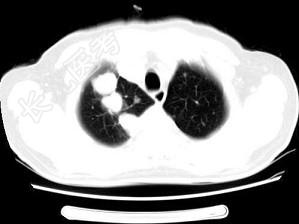

- 单项选择题男,64岁, 咳嗽半月,咯血1天, 不发热,结合图像, 最可能的诊断是 ( )

A、金葡菌肺炎

B、肺转移瘤

C、肺结核

D、结节病

E、组织胞浆菌病